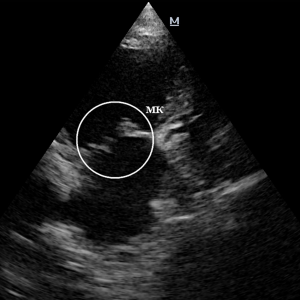

Эндокардиоз